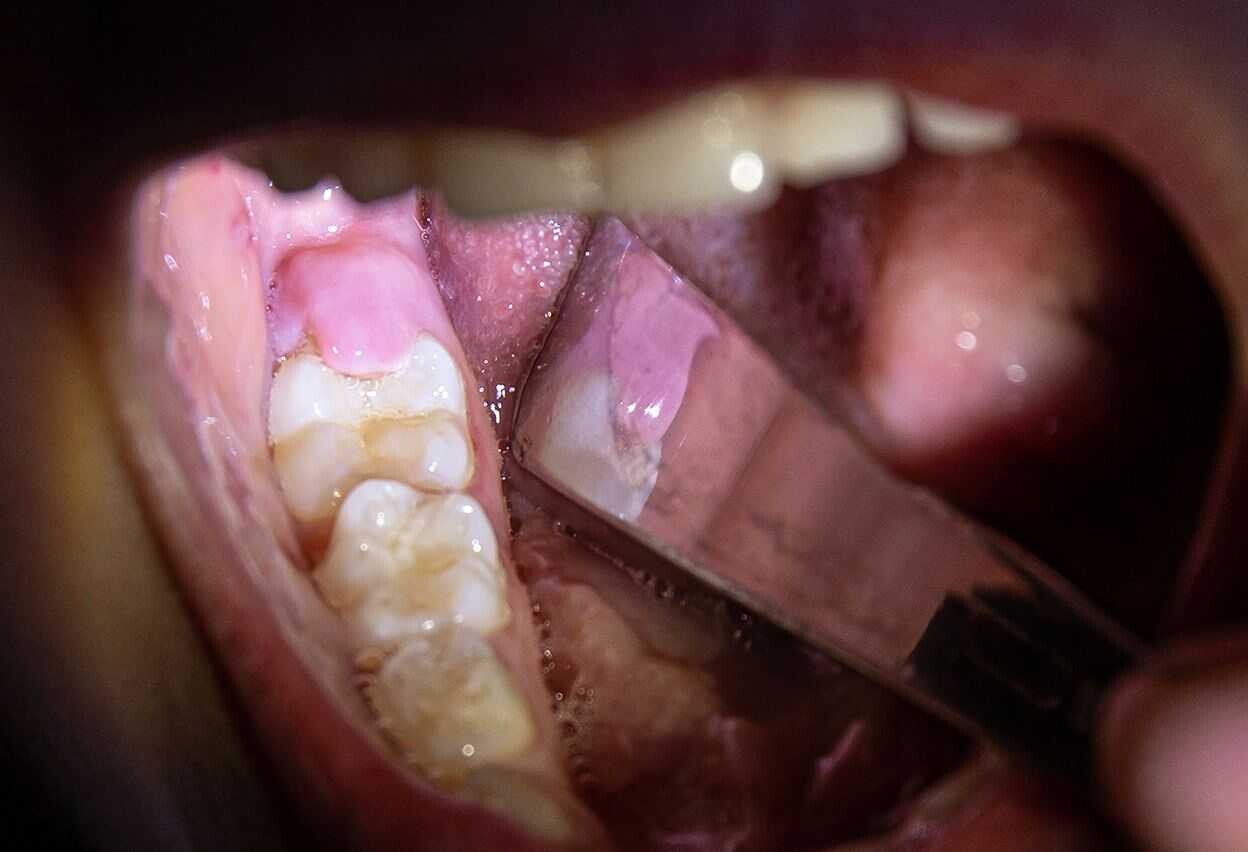

If your wisdom teeth have started to come in, you may notice that a loose flap of gum tissue has developed around them. This piece of tissue is known as an operculum, and it often develops over partially erupted teeth or teeth that do not have enough room to come in.

Learn more about issues with operculums and why they sometimes need removing.

Why Can Operculums Be a Problem?

While some operculums only partially cover a wisdom tooth, some may cover much of the chewing surface. If the flap is large, you can have an increased risk of biting the adjacent cheek tissue or the operculum itself.You can keep your enamel and attached gingiva clean with both brushing and flossing.

Operculums, on the other hand, can be difficult to keep clean since they are in the back of the mouth and because the loose tissue may trap bacteria and food debris.

If too much debris is trapped, you can develop pericoronitis, which is an inflammatory condition.  People with pericoronitis can experience bad breath, pus, and pain when eating or swallowing. If you do not treat the pericoronitis, you can experience lymph node and facial swelling.